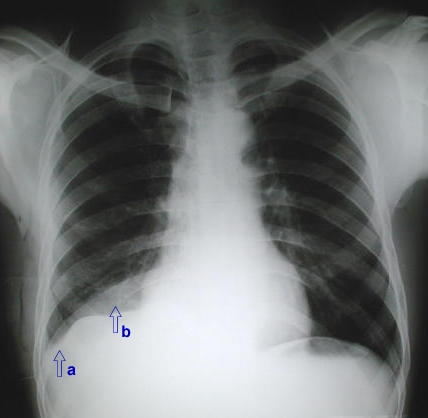

• La radiografía del tórax PA:

A su primer ingreso muestra.

- (a) - Un aumento de densidad que borra tenuemente la linea diafragmática derecha en el seno costofrénico externo , y superiormente (b), se encuentra bien delimitada.

característico de:

derrame pleural sub pulmonar.

En este caso en particular debido a su antecedente:

Hemotórax sub pulmonar

Rx. Tórax PA. en el momento agudo del trauma ,14 dias antes